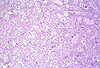

CASO N° 2 (Dr. Elismauro e Dr. Delgado)

Paciente do gênero masculino, 85 anos de idade, apresenta um aumento de volume na maxila esquerda.